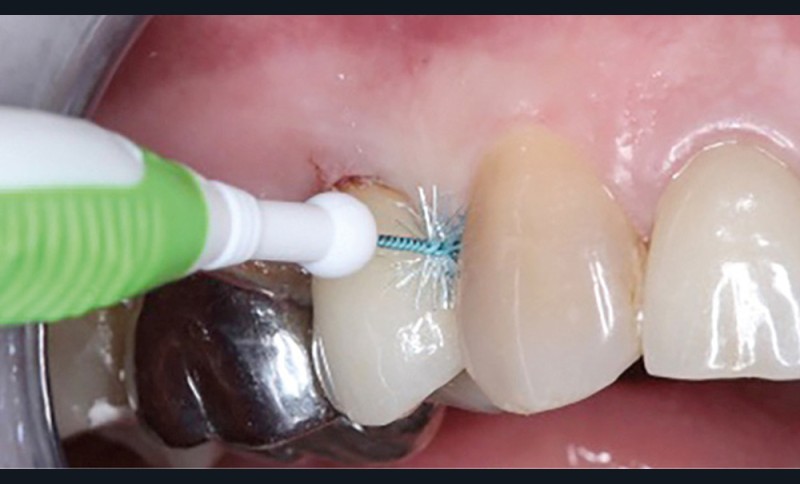

Le mode d’assemblage (prothèse vissée ou scellée) retenu peut aussi influencer la survenue d’une péri-implantite, avec une corrélation importante entre survenue de péri-implantite et présence d’excès de ciment de scellement [13, 14]. Une connexion dent-implant (prothèse dento-implanto-portée) est à proscrire, car plus propice aux péri-implantites et échecs mécaniques (fig. 4 et 5) [15, 16].